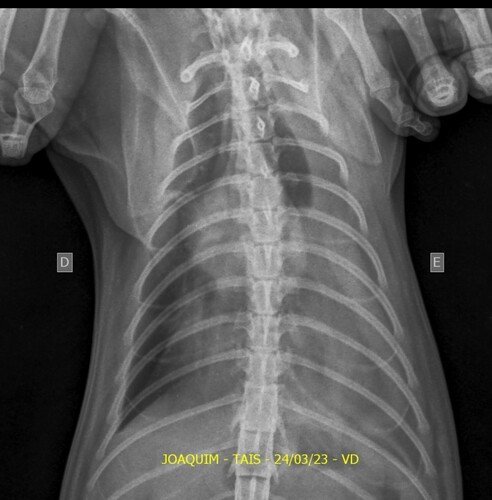

Venha aqui pedi ajudar de vocês. Meu gato, o Joaquim,sofreu um acidente no dia 14/03. Ele rompeu o diafragma e precisa de uma cirurgia urgente. Está com problema respiratório, teve umas lesões interna, uma lesão na pata traseira e não come devido o rompimento. Ele precisa fazer essa cirurgia o mais rápido possível.